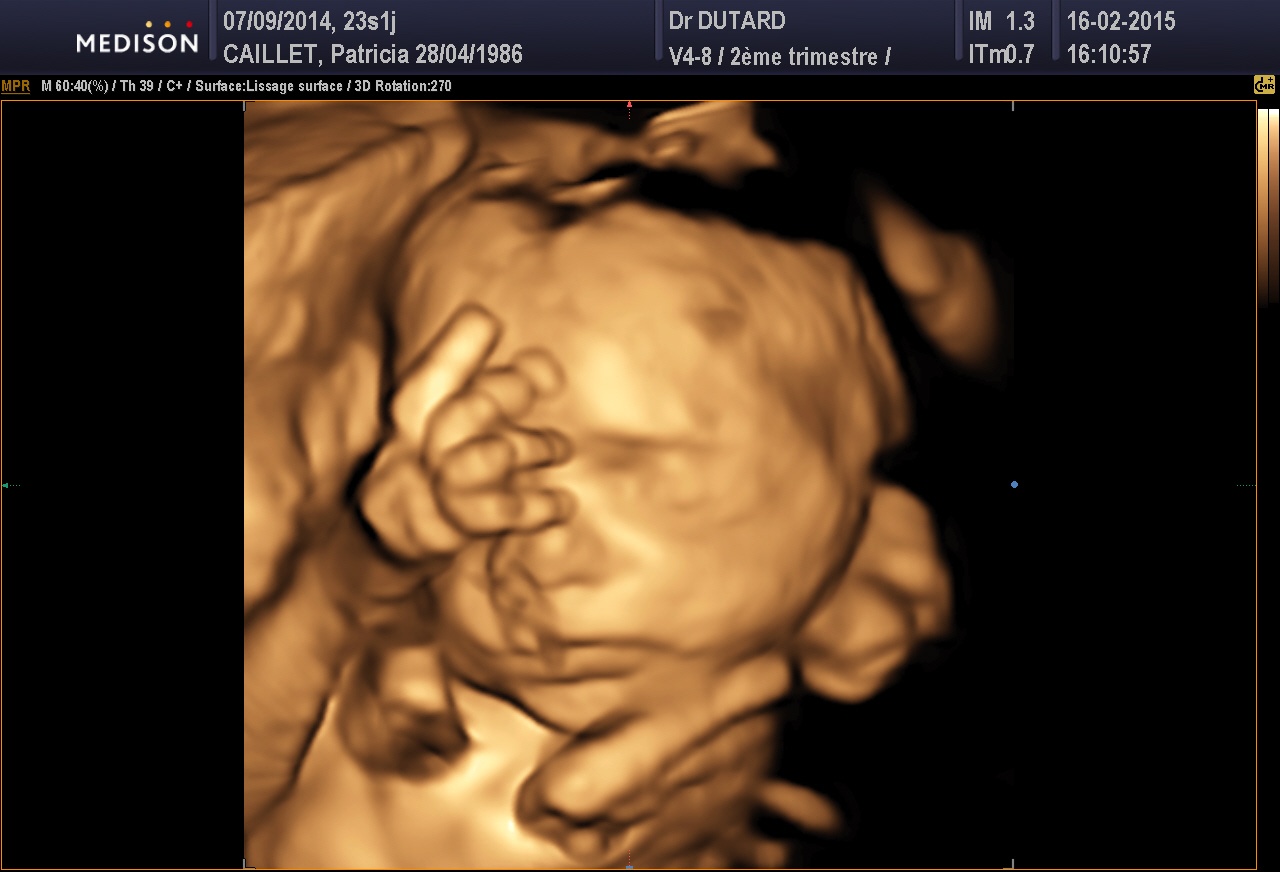

J'ai mon écho demain je vous cache pas que j'ai hâte !! Je dois savoir le sexe normalement mais aussi parce que je le sens pas trop donc je stress on est toutes pareils je crois ....

de son ptit bonhomme,puis on s en lasse pas de regarder ses echo surtout en 3d c est le top